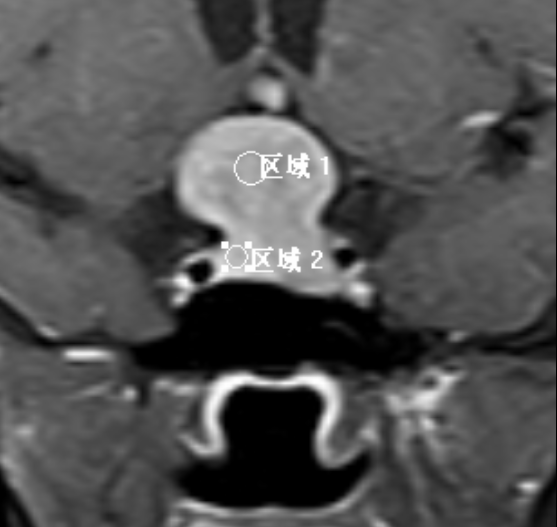

垂体-T2